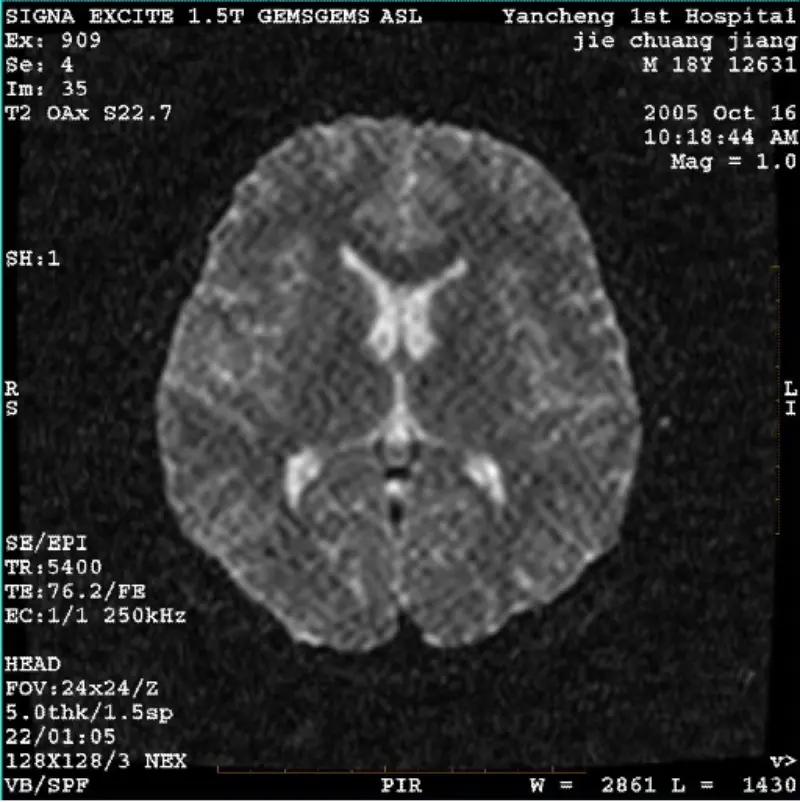

Preberi večSISTEM: 1.5T Signa Twin Excite II (različica programske opreme 11.0M4) TEŽAVA/SIMPTO DWI (način povečave in celoten način) in fiesta (način povečave in celoten način) imata sliko viden artefakt iz mrežastega ali kordurastega materiala, ne glede na uporabo tuljave ali glave tuljava, druga ruti......